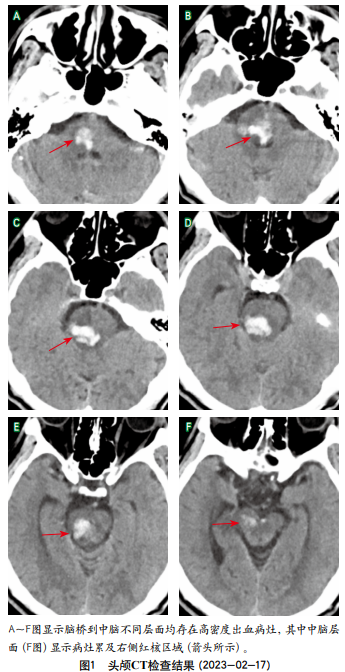

影像学检查:头颅CT(本次入院前3个月)示脑干出血(约5 mL),并疑似破入第四脑室(图1)。复查头颅CT(本次入院前2个月)示脑干出血较前吸收,右侧齿状核可见斑片状低密度影(图2)。